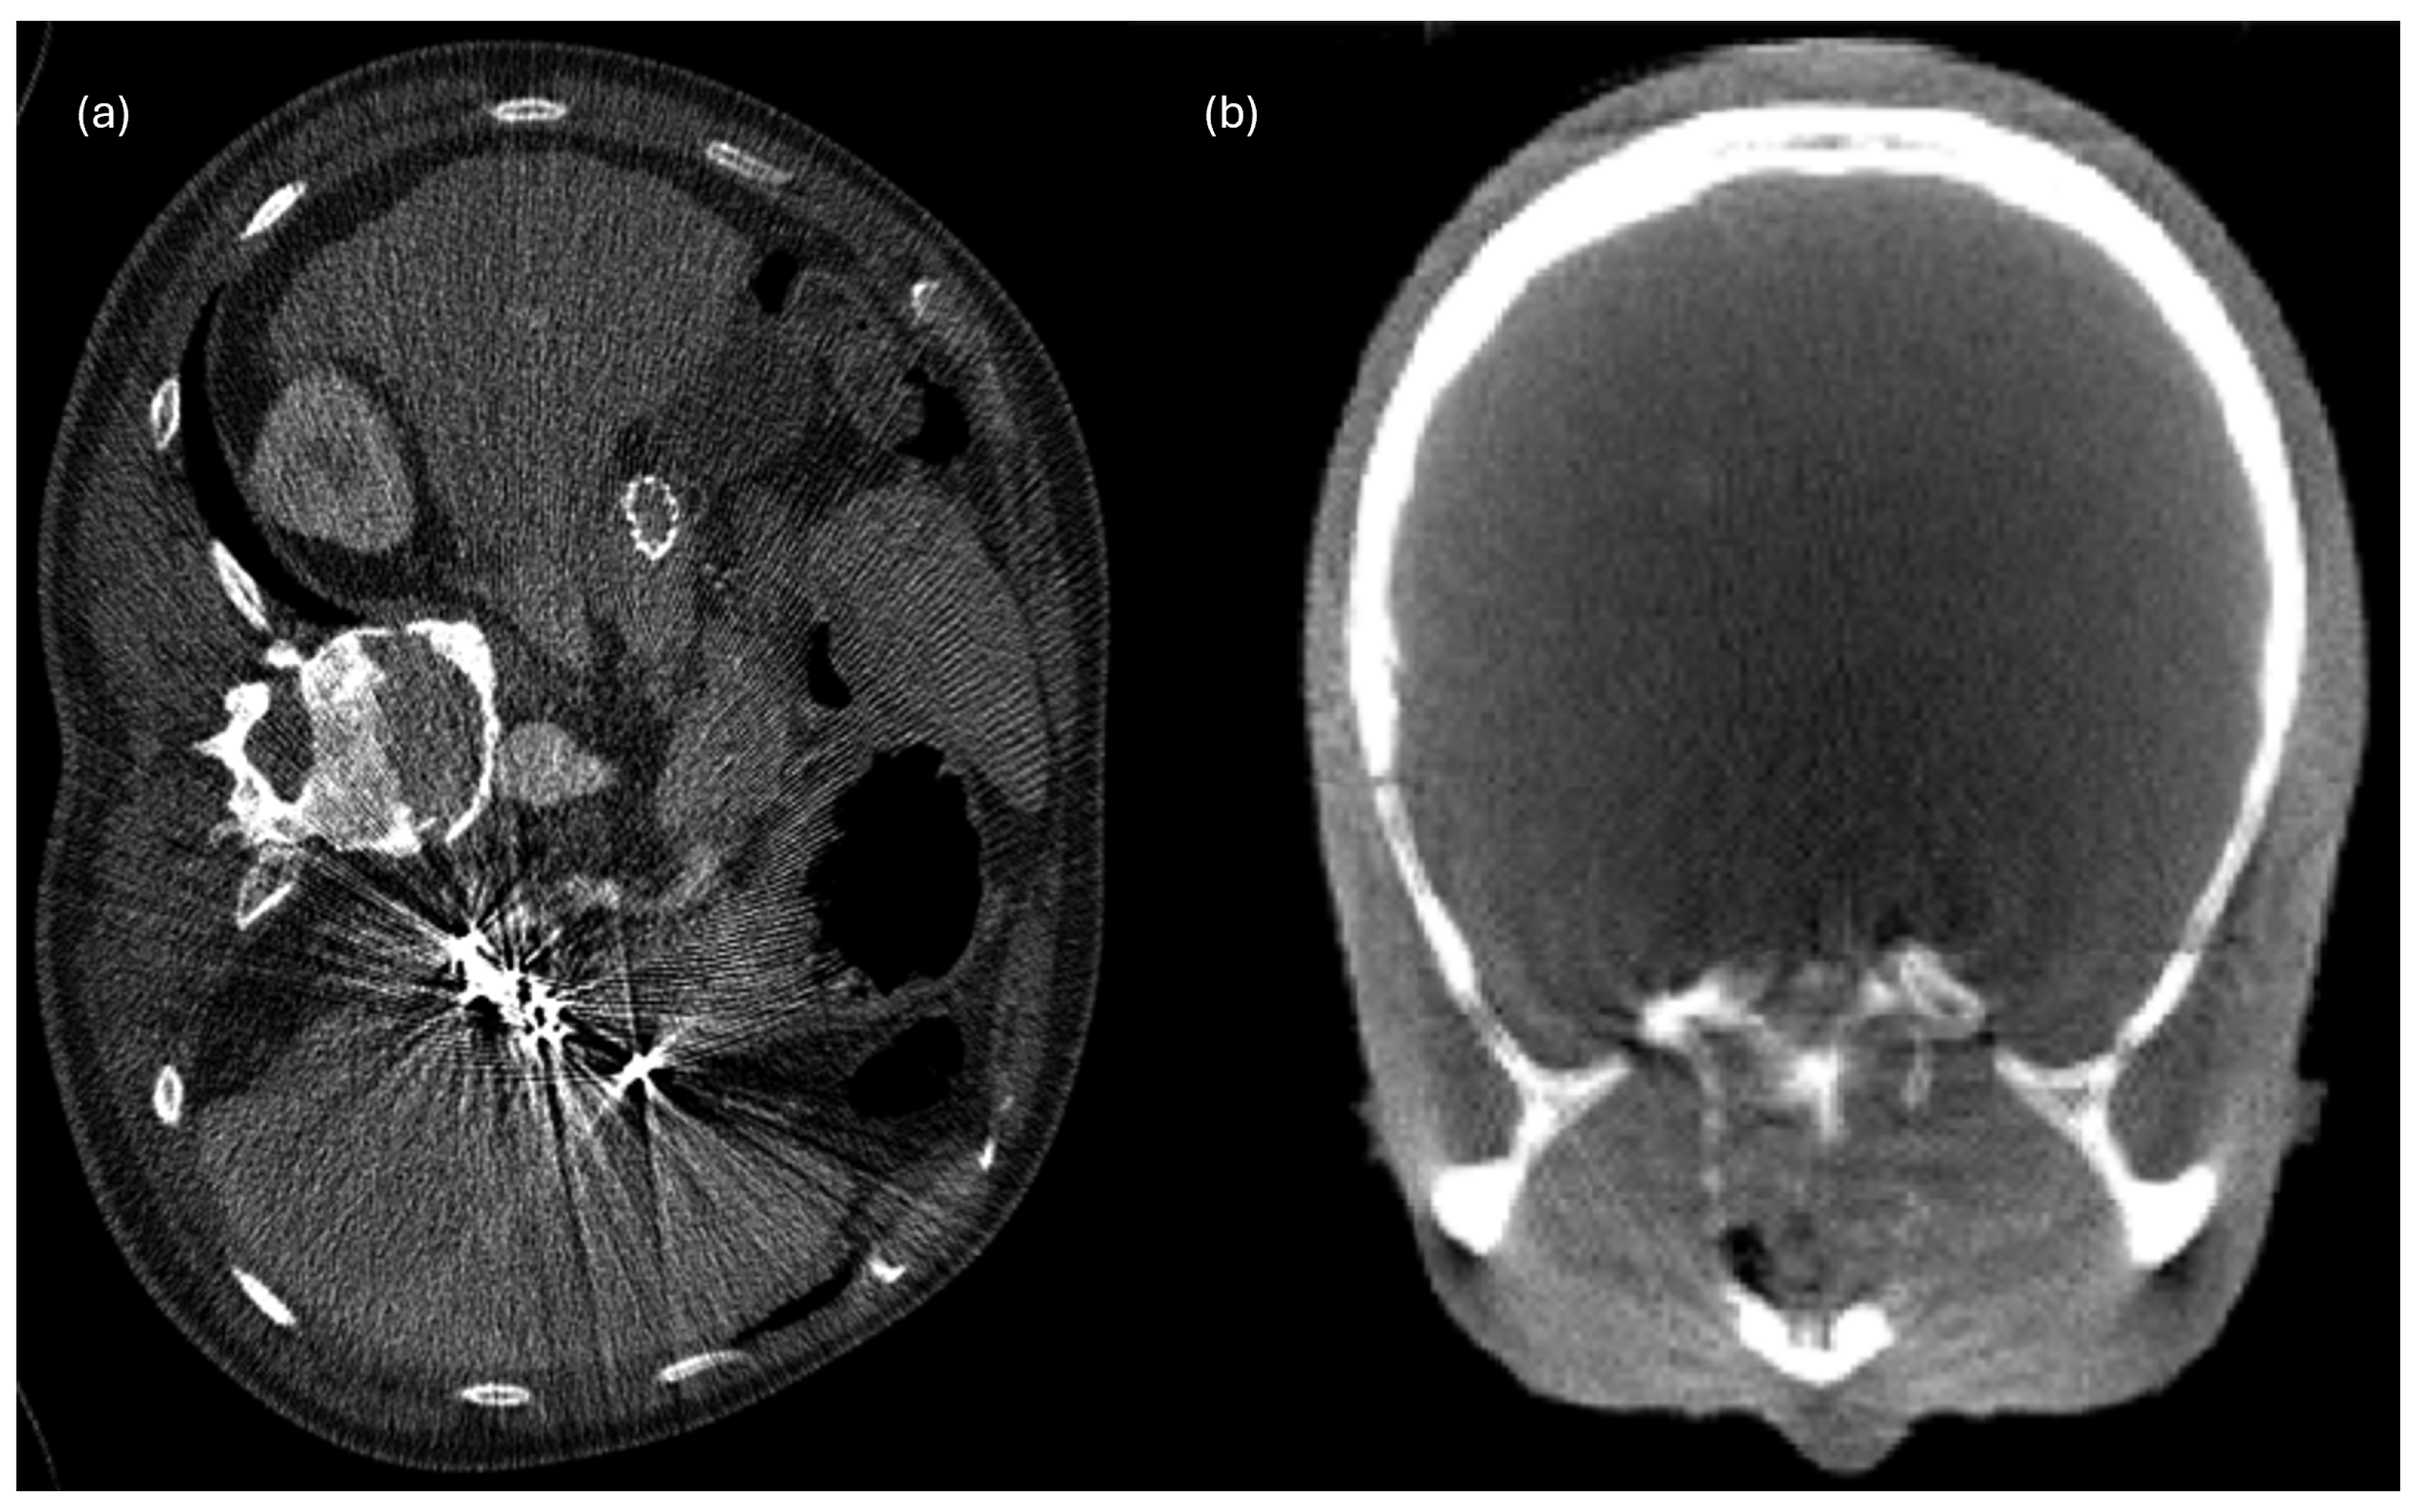

6.2. Beam Hardening Streaks and Cupping Artifacts

6.3. Noise

| Beam hardening | CT | First-order, texture | Feature bias, intensity distortion |